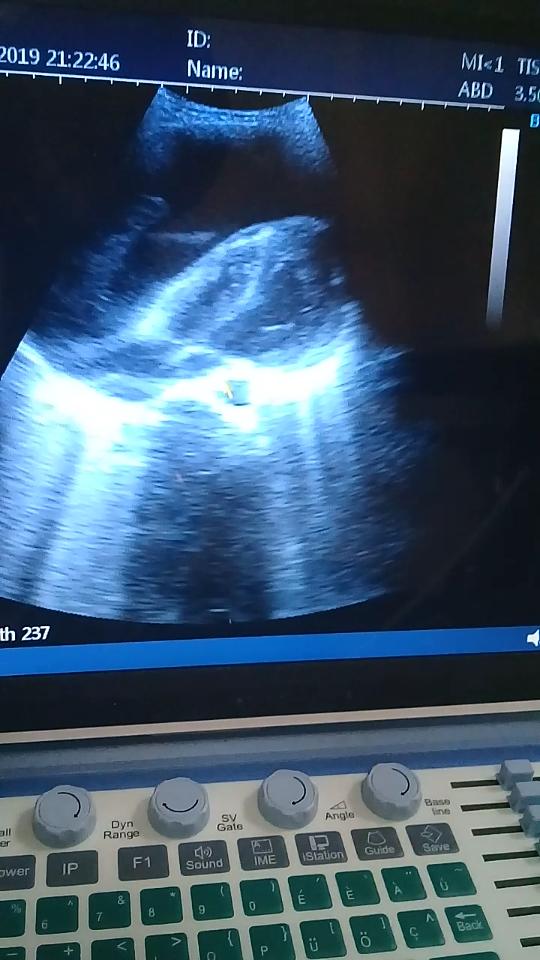

Pericardial effusion with Dr. Francis Sakita

In this edition of the Compass, I will be sharing a case which presented to the KCMC emergency department after being referred from a peripheral hospital. The patient was a 31 yearold female who presented with a complaint of coughing nonbloodstained sputum for one month; this was accompanied by shortness of breath in the supine position and central chest pain. The patient denied history of fever, night sweats or loss of weight. The primary survey was unremarkable except for distended jugular veins and crepitations on the right supramammary region.

Vitals signs were: BP 90/50 mmHg, HR 129, RR 30, SpO2 94% on room air, and a temperature of 37⁰C.

Secondary exam revealed muffled heart sounds and a distended abdomen due to ascites.

Bedside ECG revealed sinus tachycardia, low voltage rhythm and electrical alterans (see below).

These findings prompted us to perform a bedside cardiac ultrasound which showed massive pericardial effusion with RV collapse (see below).

Ultrasound-guided emergency pericardiocentesis through the subxiphoid region was performed and approximately 300ml of hemorrhagic fluid was drained. Immediately after draining the effusion the patient’s blood pressure and heart rate normalized.

Take home points in this case: early identification and treatment of pericardial effusion (and the skill set needed to interpret the ECGs and performing the bedside/field ultrasound) can save lives.